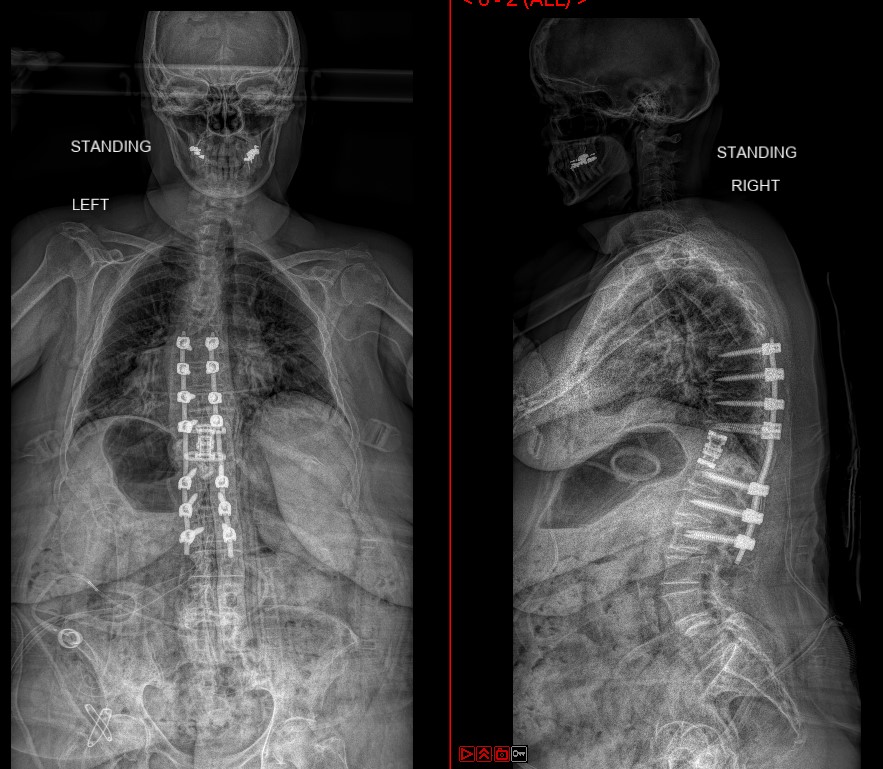

Thoracic Corpectomy